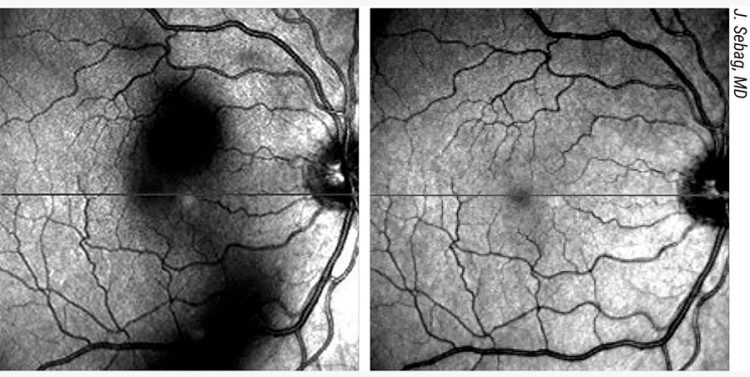

Figura 4. Las opacidades del cuerpo vítreo proyectan sombras sobre la retina (imagen a la izquierda) que los pacientes perciben como “moscas volantes”. Éstas se desplazan con el movimiento de la cabeza y las sacadas oculares, mostrando una dinámica de movimiento característica (“retraso” y “rebote”) debido a las propiedades viscoelásticas del vítreo. Tras una vitrectomía limitada, el vítreo central está limpio (imagen a la derecha), cesan los síntomas de moscas volantes y se normaliza la sensibilidad al contraste.6-8